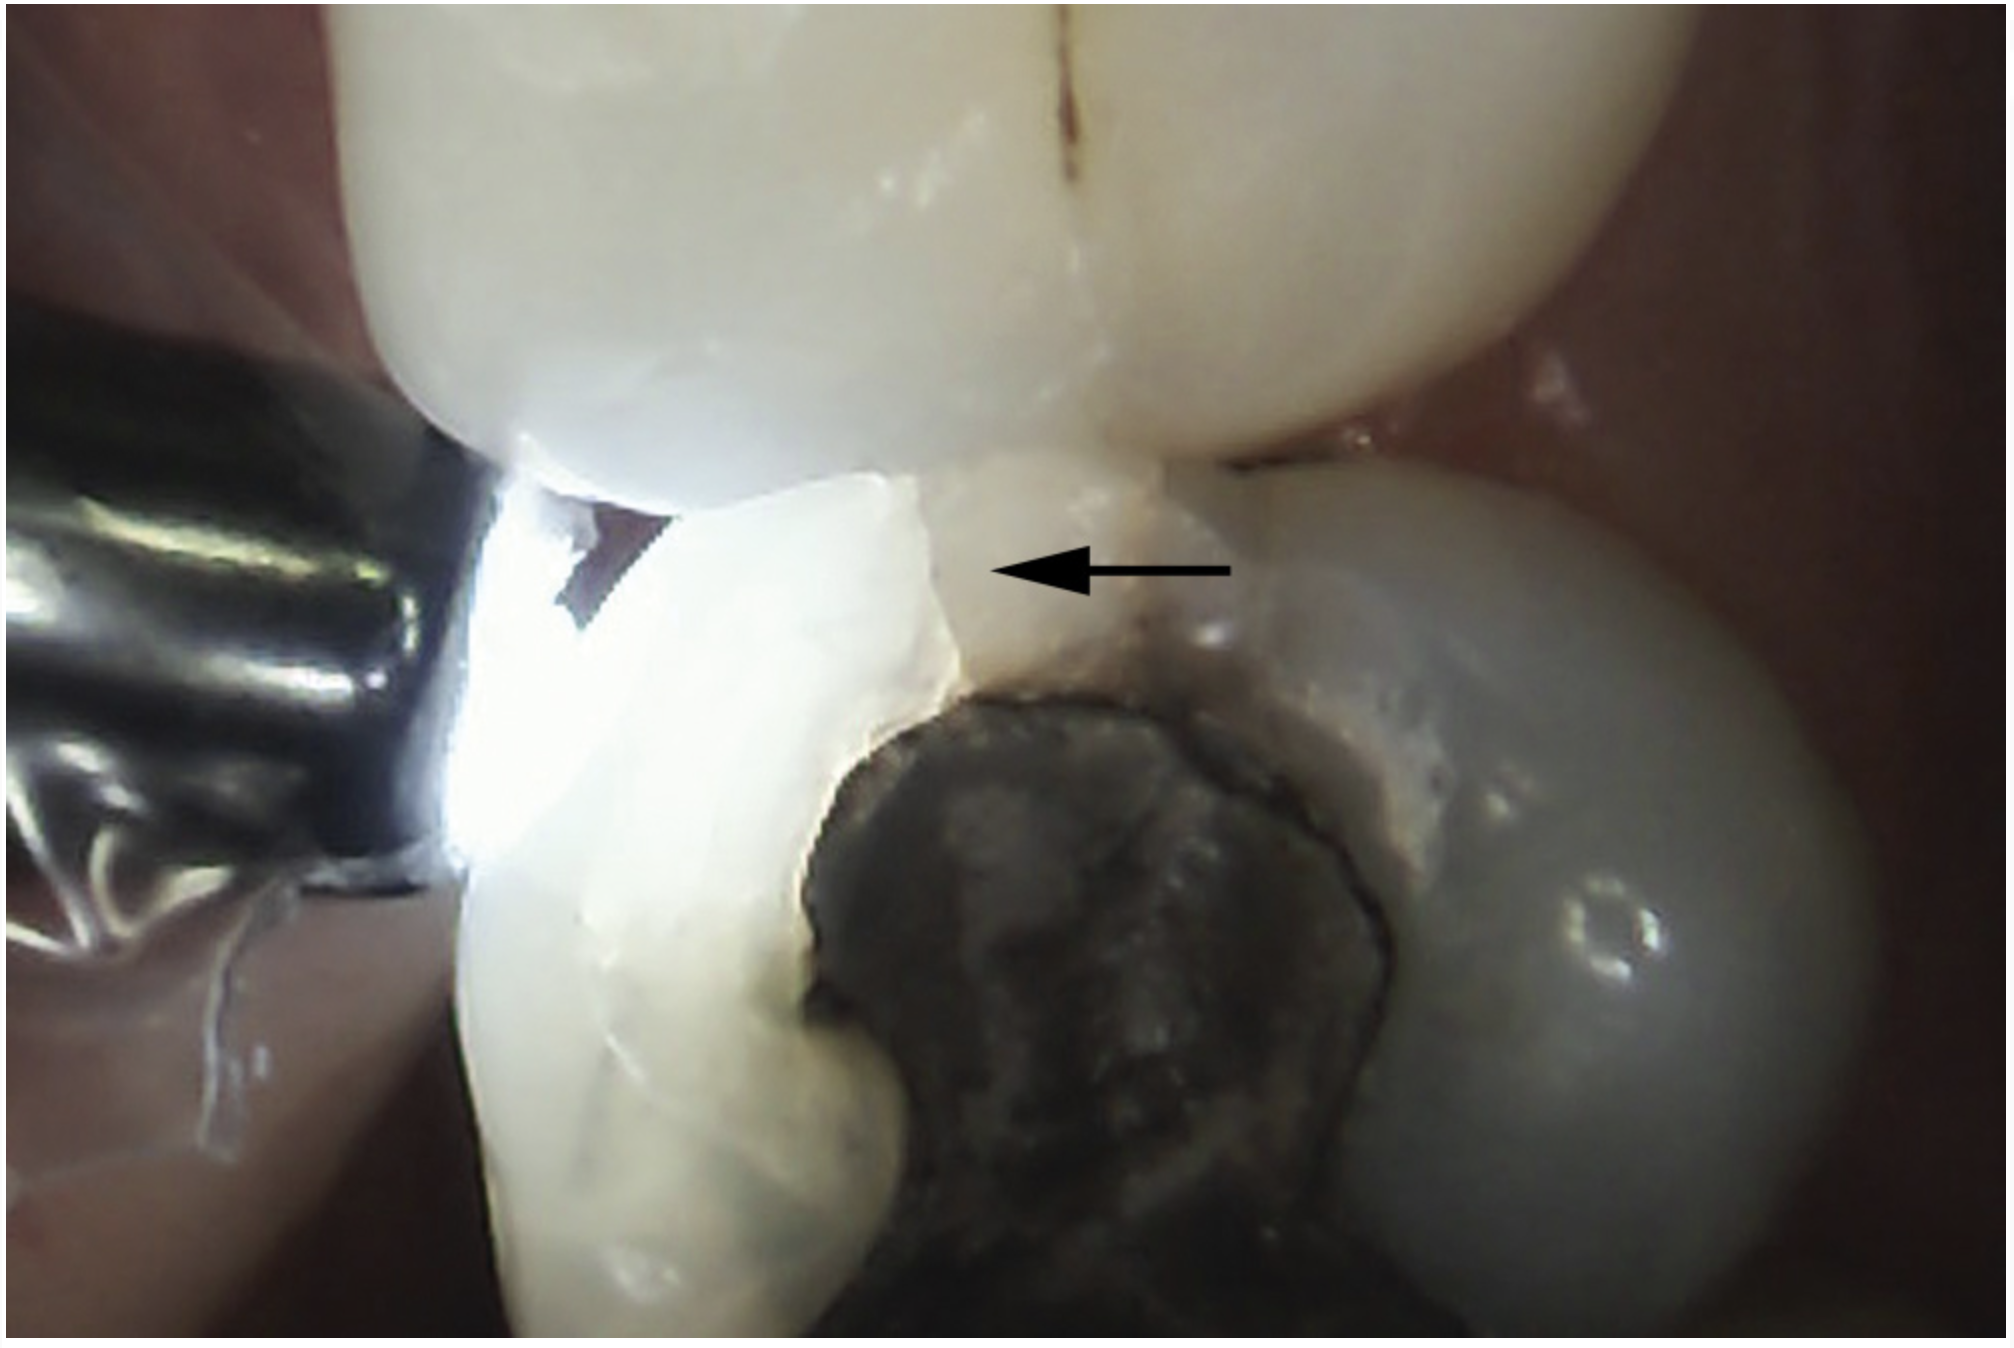

Fig 11. Exploratory fissurotomy and methylene blue dye staining revealing an underlying deep dentin crack in tooth shown in Fig 10.

Figure 11